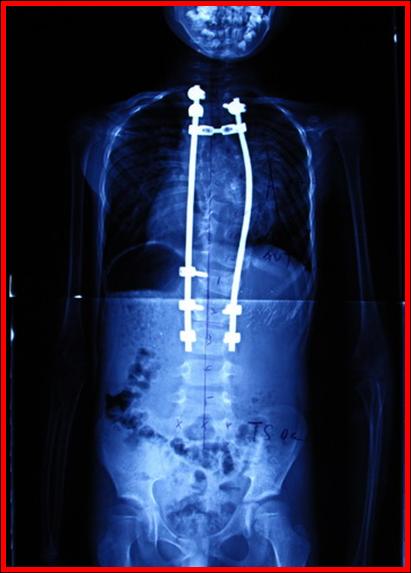

术后X线